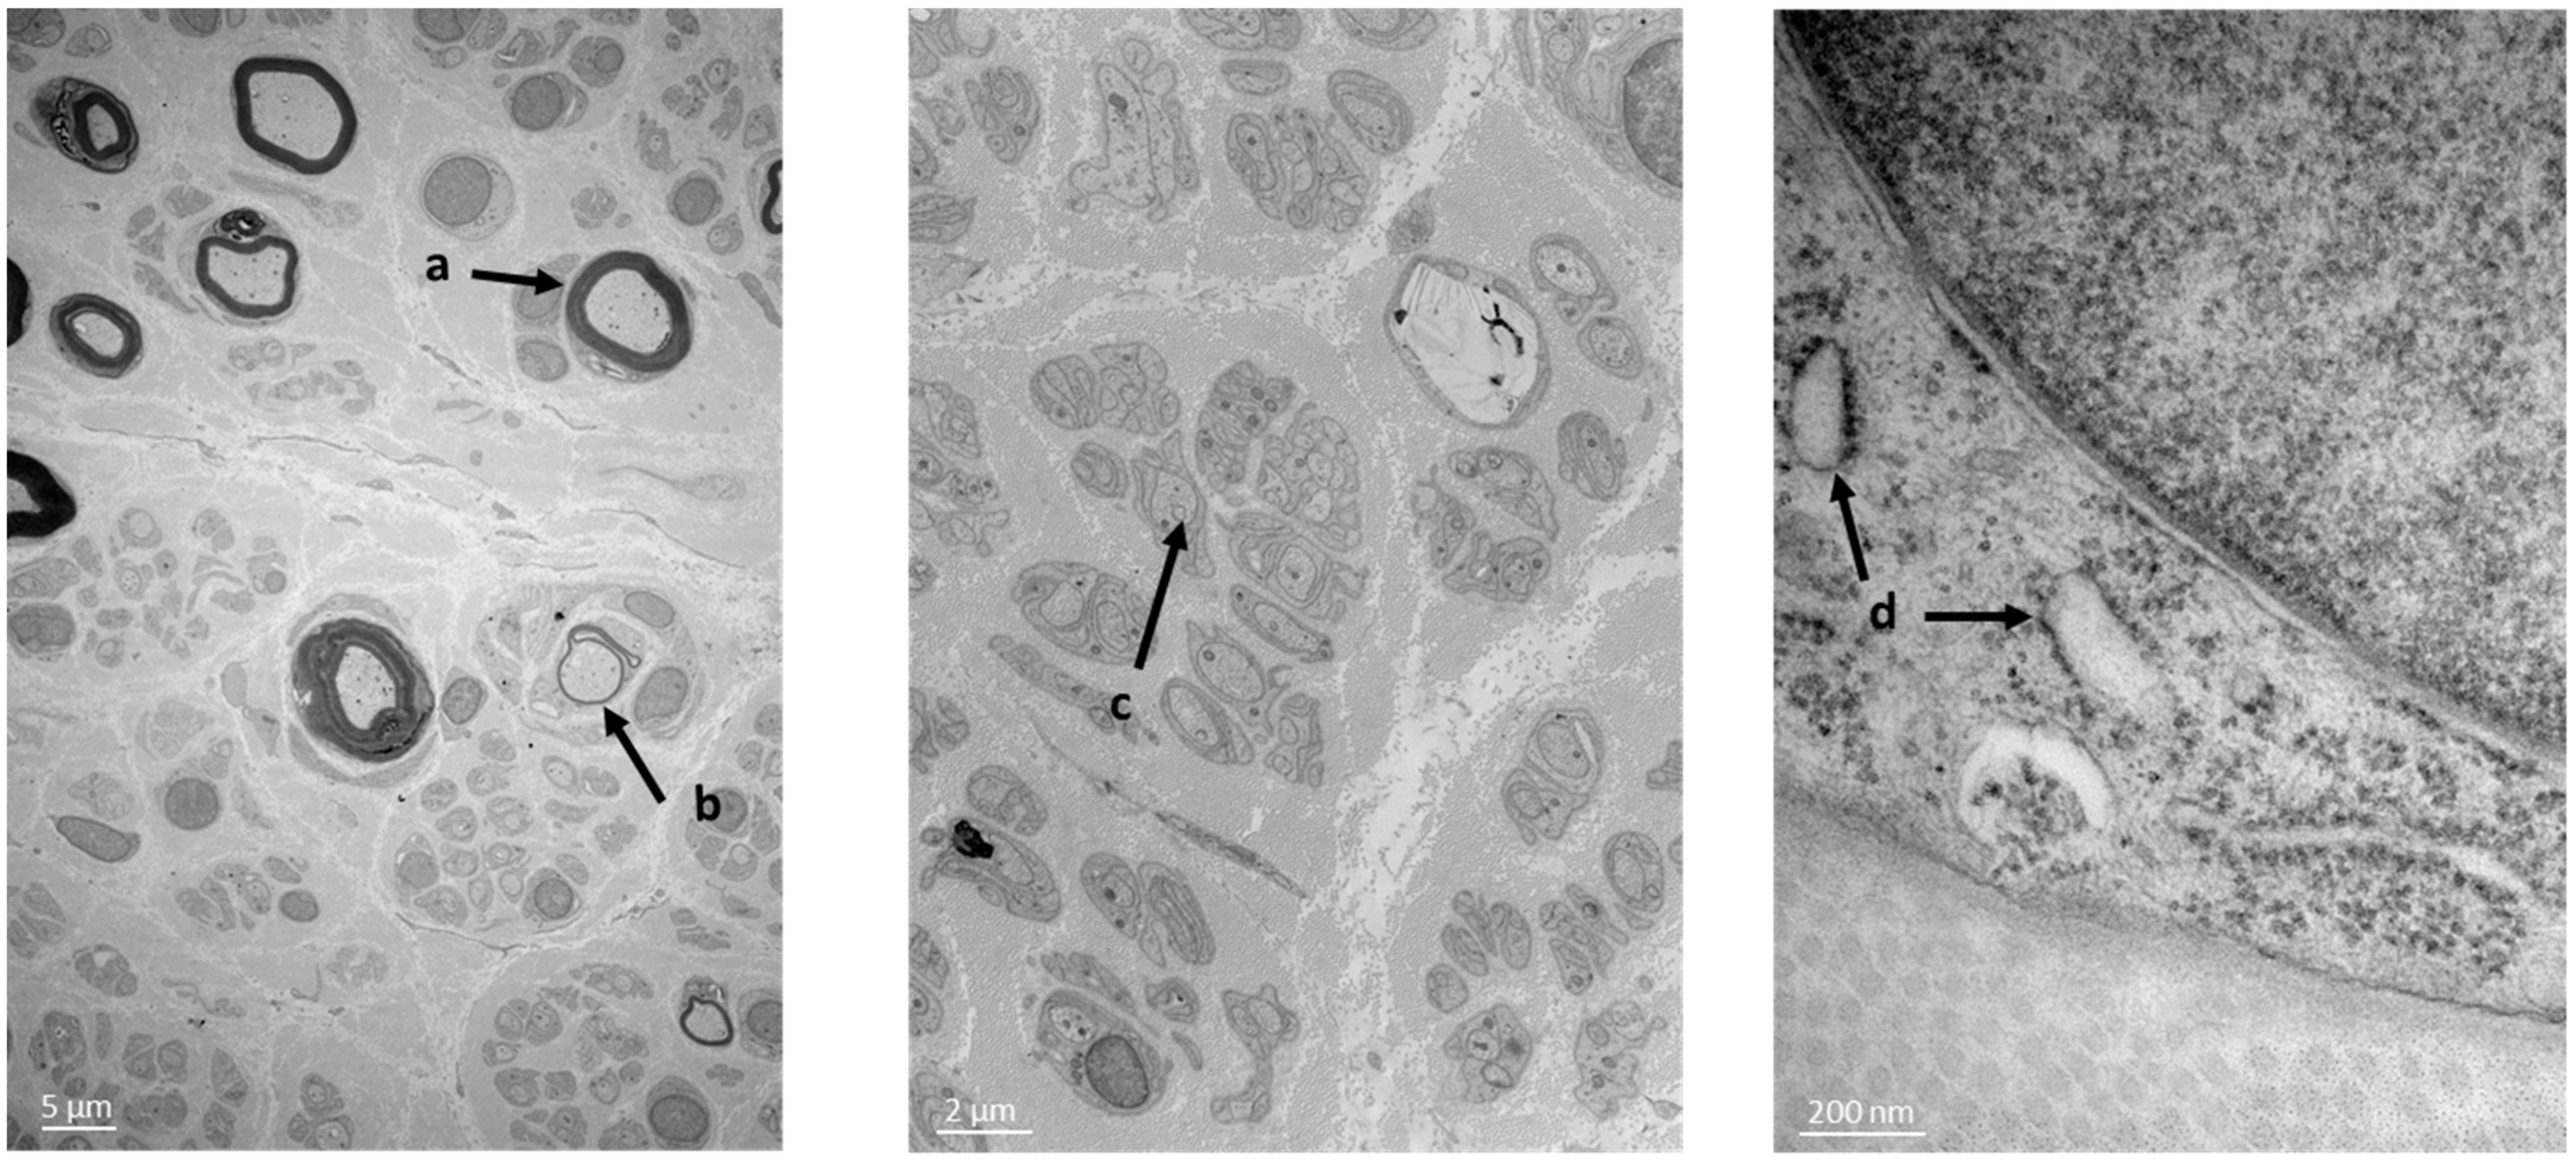

A sural nerve biopsy was performed. Semi-fine sections on epon resin revealed a very severe rarefaction of the myelinated fibers which appeared to be more or less homogeneous between the fascicles. This damage concerned both large- and small-diameter fibers. A large number of axons with too thin of a myelin sheath in relation to the axonal diameter were present, which indicates a demyelinating–remyelinating process. Regarding the aspect of the endoplasmic reticulum (ER) (Figure 1), it seems that the ER is sometimes dilated without being interconnected, like previously described [9]. No interstitial tissue abnormality was observed.

Figure 1. Patient’s nerve biopsy. Semi-fine sections on epon resin revealing rarefaction of the myelinated fibers. Presence of axons with too thin of a myelin sheath in relation to the axonal diameter, supporting a de-myelinating–remyelinating process. (a) Normal myelinating fibers; (b) de-myelinating–remyelinating fibers; (c) unmyelinating fibers; (d) ER presenting a suffering morphology.

ATL3 codes for atlastin-3, a protein that plays an important role in the biogenesis and structure of the ER tubular network. Electronic microscopy analysis of the sural nerve biopsy of our patient showed abnormal aspects of the patient’s ER, as the ER vesicles appeared more swollen. According to previous studies, a disruption in the ER network has been observed in cells expressing the mutant ATL3, suggesting a dominant-negative effect of mutant ATL3 [5,9,13]. However, an analysis of the patient’s nerve tissue by using a 3D microscope would be necessary in order to determine the effect of the deletion presented in our patient on the 3D aspects of the ER network.